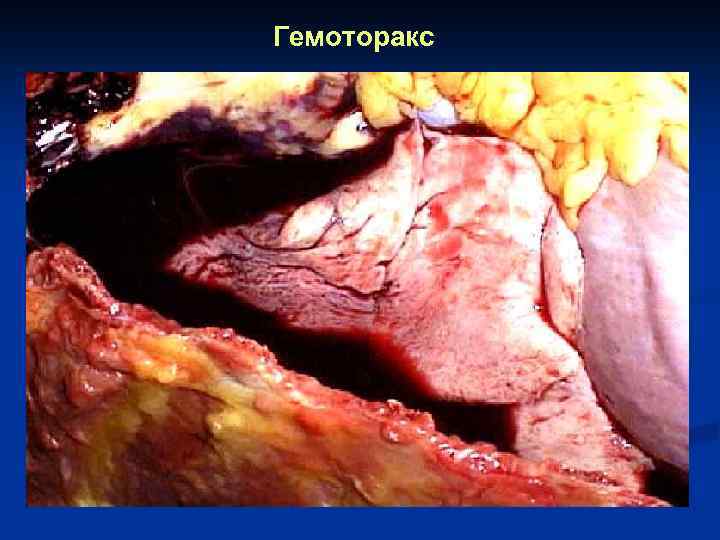

Гемоторакс